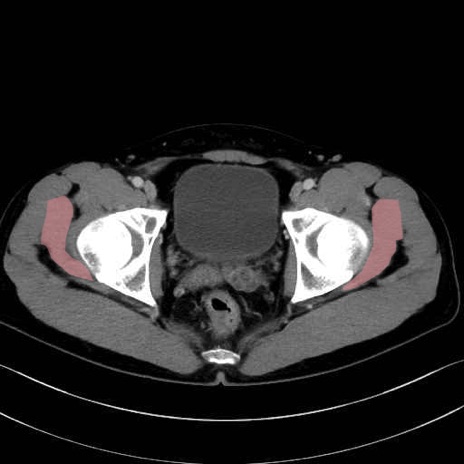

小殿筋 (Gluteus minimus)